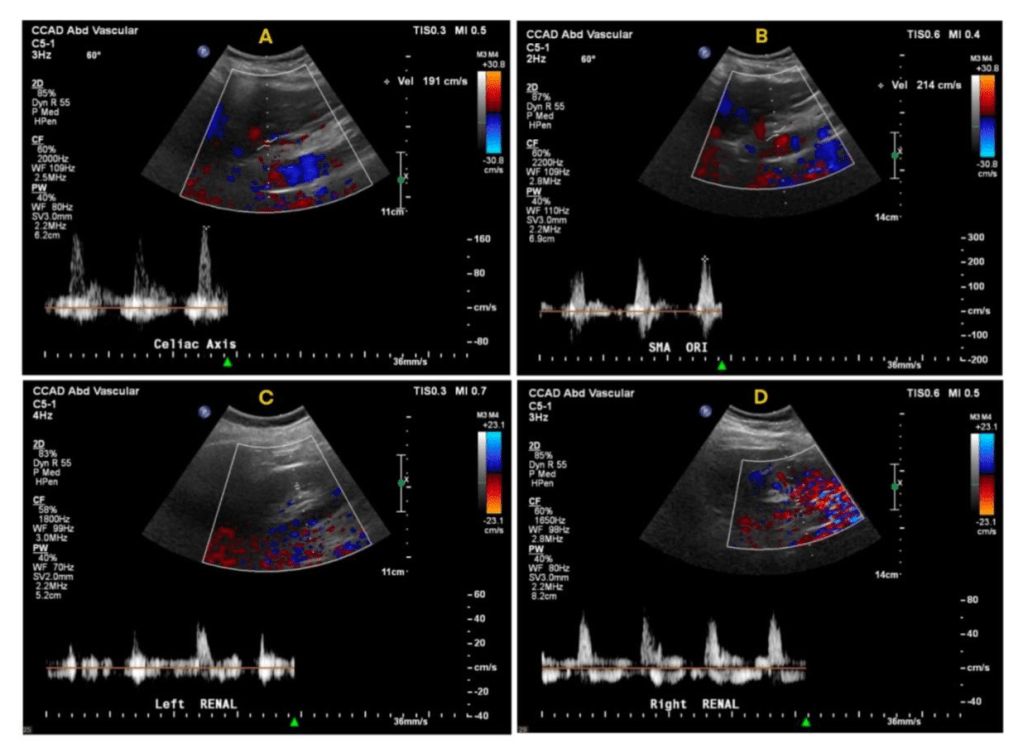

Innovation #3: Assessing for Visceral Malperfusion before Surgery for Aortic Dissection

The typical scenario for a sad ending is this: a patient undergoes emergency surgery for an ascending aortic dissection. The operation ends in the middle of the night. The morning labs show a lactate of 10 which had been rising since the end of the operation from a high borderline level of 2. The urine output also dropped to zero. The patient remains intubated and has palpable femoral pulses, but now has a distended abdomen full of bowel gas, and is unable to report pain. The decision is made to get a CTA on top of the ones the patient received preoperatively which nearly guarantees permanent renal failure and need for hemodialysis. The descending aortic portion of the dissection is noted to be causing a malperfusion of the SMA and left renal artery, and there is pneumatosis of the small bowel through transverse colon which are resected after revascularization. The patient recovers with a jejunostopy and lifelong TPN and hemodialysis. This sad scenario is what I thought about when I was asked to assess a patient intraoperatively without a femoral pulses after an aortic dissection for possible visceral malperfusion. The question was if CT with contrast was indicated. Having an RVT credential (I’m old), I frequently do my own scans, and have found under general anesthesia, the abdomen is easy to scan well. The patient is typically prepped from neck to toes for the operation, so sliding in with an abdominal probe was simple. It is possible to get excellent windows on the visceral segment abdominal aorta with long axis and short axis views of the celiac axis, SMA, renal arteries, and iiac and lower extremity arteries (figure below).

At CCAD, the patients also get a TEE, and the arch and descending thoracic aorta is well visualized. That first patient underwent a femorofemoral bypass for the lower extremity malperfusion, and I found that the left renal artery had obstruction, but the right did not. The patient was reassessed at the end of the case and good visceral perfusion was seen at that point. I realized I was onto something, and whenever possible now for ascending aortic dissections, myself or the vascular tech is called to evaluate the visceral and lower extremity arteries at the beginning of the case, avoiding contrast studies. We are submitting the experience as an abstract for the STS conference.